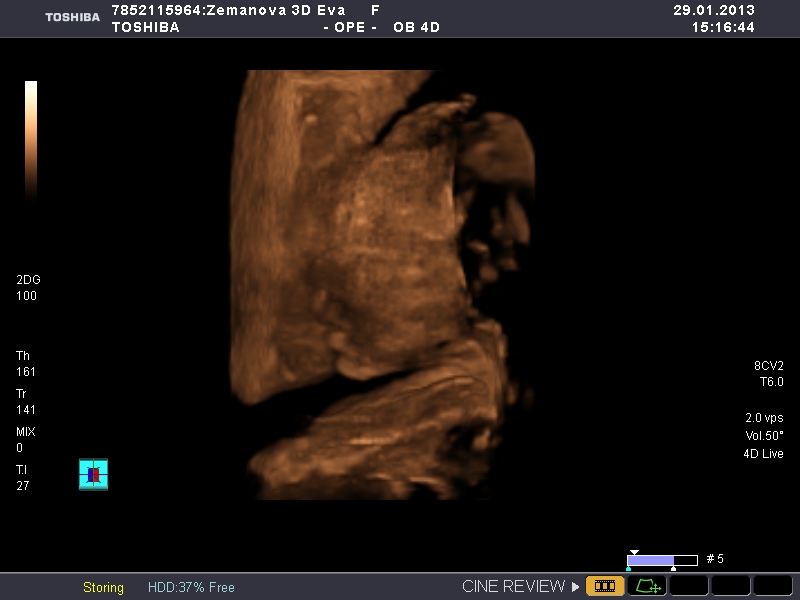

Ráno v 7:30 jsem opustila teplo svého domova a odjela sednout si k počítači a pracovat. Dosedla jsem v 8:10 a do teď u toho počítače dřepim (pár přestávek jsem měla, abych nekecala) a odhaduju, že ještě tak 2 hodiny tu dřepět budu a ráno v osm už mám zase vyzvedávat klienta a jet někam do horoucích pekel. A PAK MI NĚKDO VYSVĚTLETE, JAK TO NAŠI MYSLELI, KDYŽ ŘÍKALI,AŤ SE UČÍM, ABYCH MĚLA HEZKOU PRÁCI A MOHLA SI UŽÍVAT!?! jediný co mě s tím smiřuje, že můj hodný muž přijel a pomáhá mi, abychom to měli rychleji a má "prolhaná" matka je ve vedlejší kanceláři a dělá taky... Jestli se ve čtvrtek ukáže, že čekáme děvčátko, tak ho vychovám, aby se dobře vdalo a může být klidně úplně blbá.... 😀